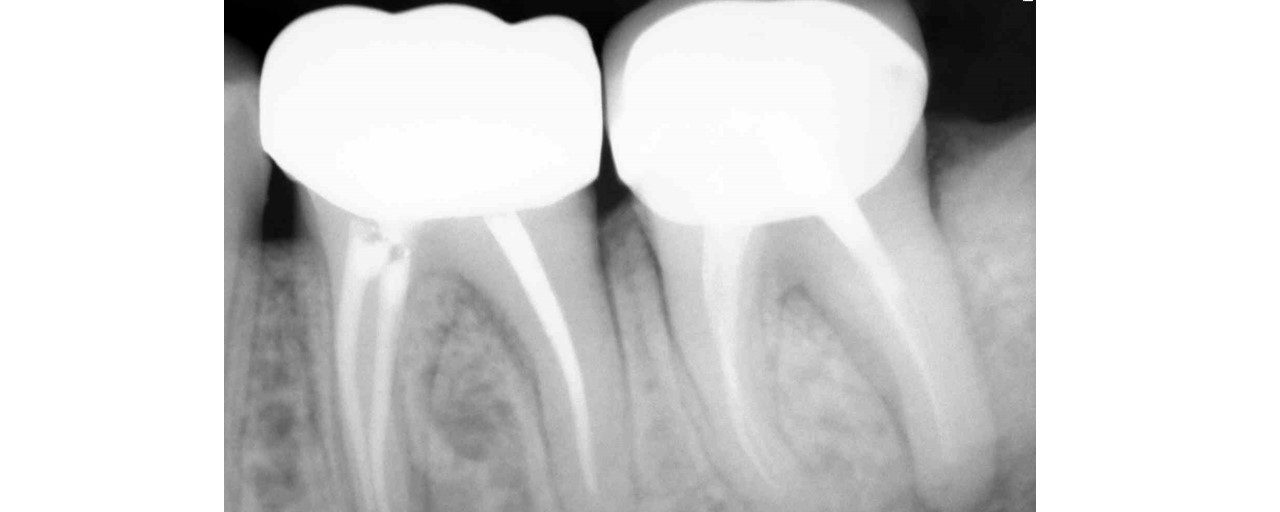

Selective Re-treatment of Distal Root

Patient came in with a sinus tract and lesion in the distal root. I Re-treated just the distal root alone. sinus tract disappeared after 2 weeks of Caoh.